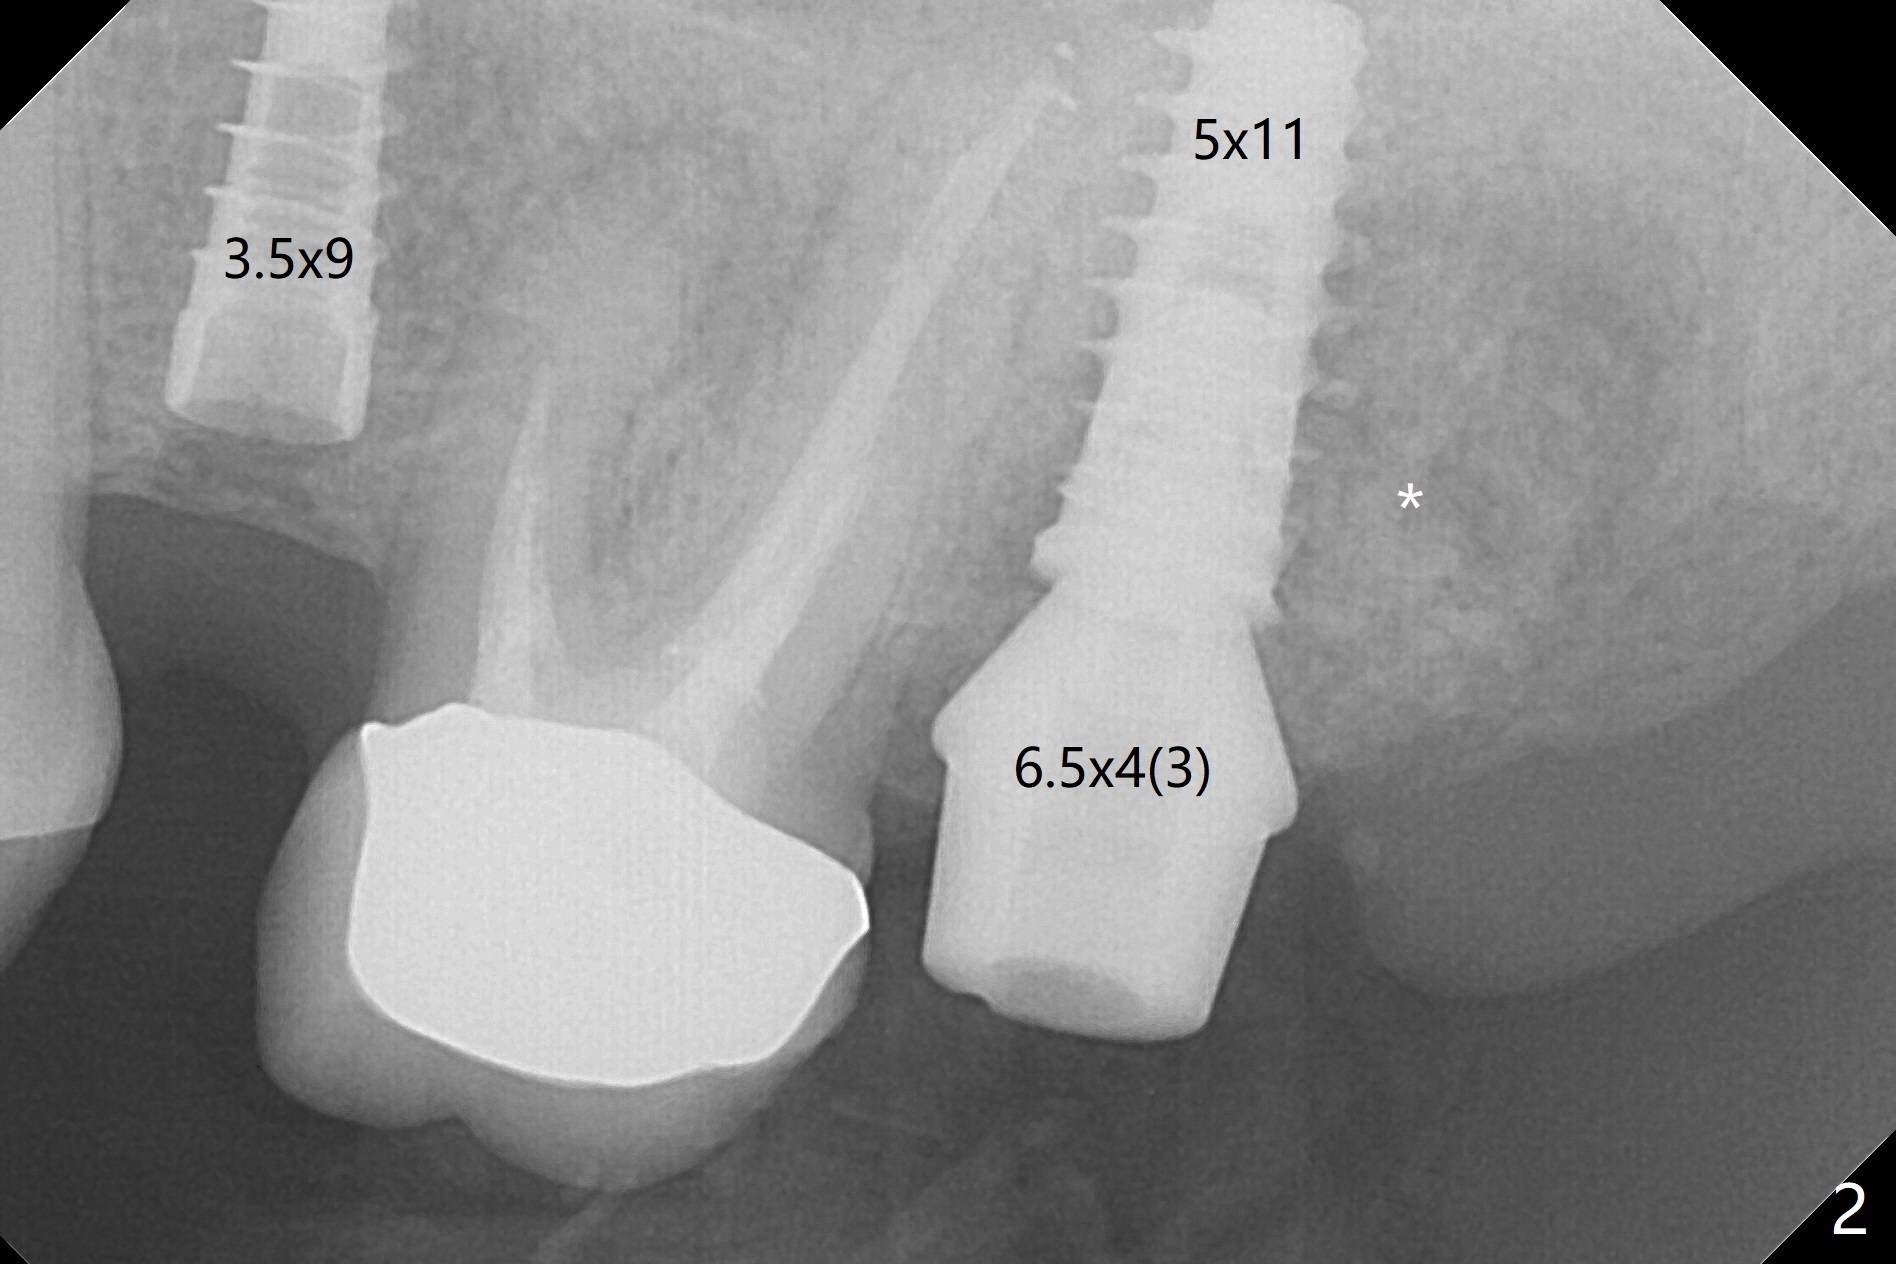

The palatal gingival margin of the tooth #15 with vertical root fracture is low, consistent with the low palatal plate after extraction (Fig.1 >). With IS guide, a 5x11 mm IBS implant is placed in the septum with >5 mm the palatal gap. After underprep in depth, a 3.5x9 mm achieves primary stability (Fig.2,3). The palatal defect is repaired with allograft (*) and 2 pieces of PRF membrane. The palatal soft tissue defect appears to have been repaired 6 months postop (Fig.4,5). When a narrower abutment with longer cuff is placed at #15 (6x4(4) mm in Fig.6, as compared to 6.5x4(3) mm one in Fig.2), there is no gap between the implant and abutment. In contrast there is one at #13 (Fig.6 <) when a 4x4(4) mm abutment is seated following removal of a 4x4 mm healing abutment. After use of a 4.6 mm profile drill, the gap disappears (Fig.7). Impression is taken.